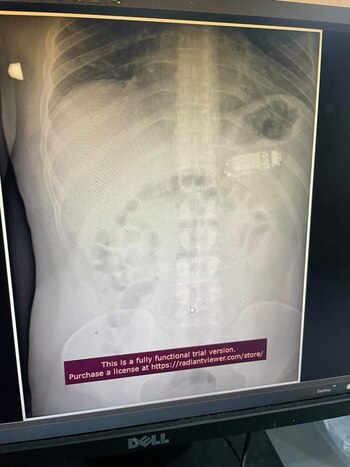

Afortunadamente, la cirugía se desarrolló sin problemas y el médico sacó el teléfono de su estómago. Telaku publicó en facebook fotos del teléfono, así como radiografías e imágenes endoscópicas. Estaba dentro del estómago del hombre.

“Recibí una llamada sobre un paciente que se tragó un objeto y, después de realizar un escaneo, notamos que el teléfono se había dividido en tres partes”, dijo Telaku a los medios locales en Kosovo.

En las fotos se puede apreciar al médico y su equipo ubicando y recuperando el teléfono del estómago, una operación que tardó dos horas hasta que retiraron el dispositivo.